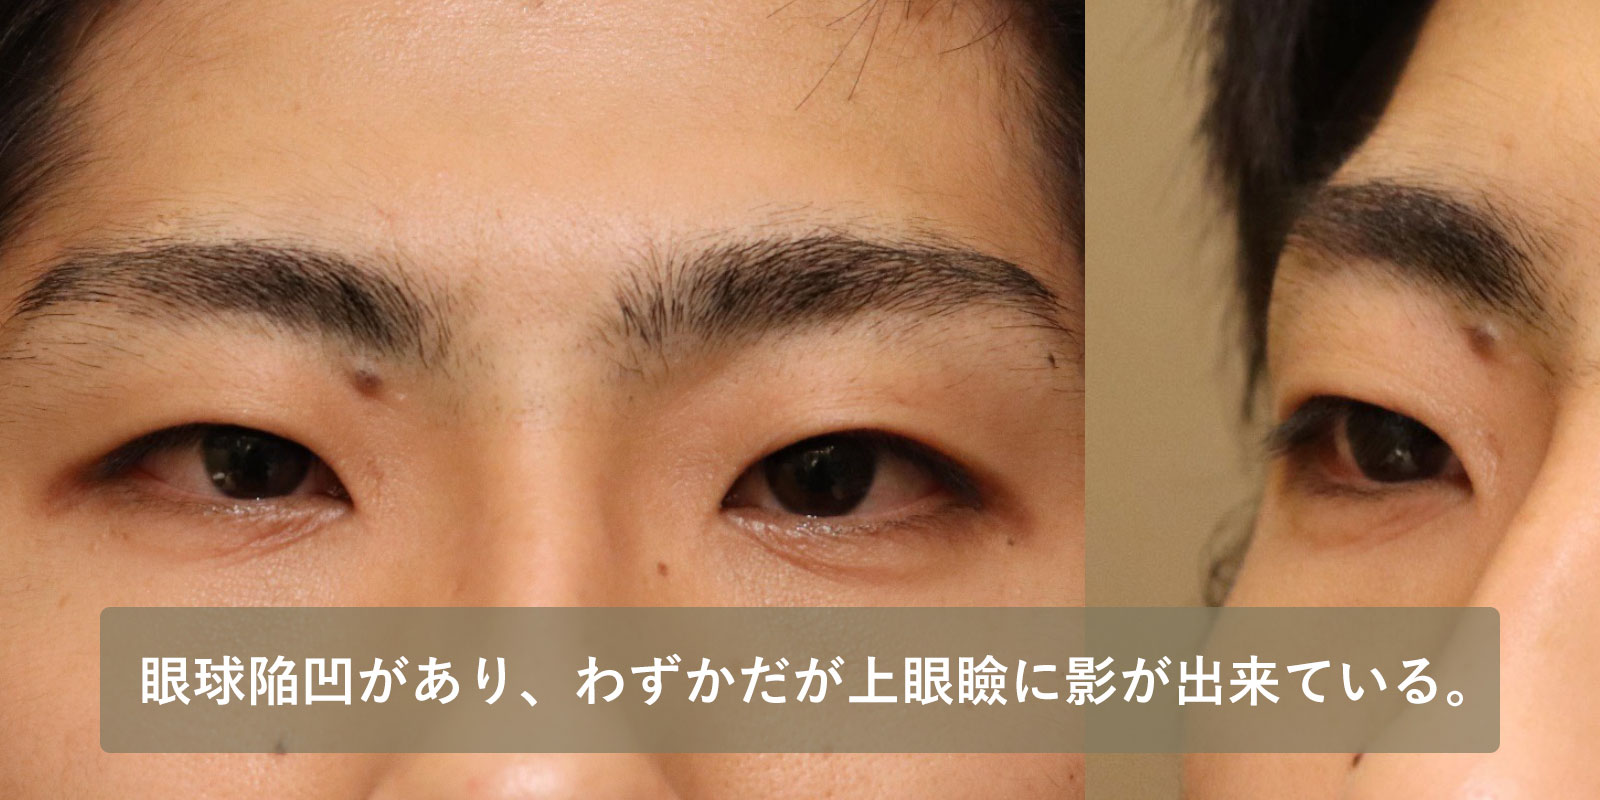

| 術前 | 眼球陥凹があり、わずかだが上眼瞼に影が出来ており、眉毛よりまぶたが凹んでいる。 |

|---|---|

| 術後 | まぶたが膨らみ、影が無くなり、眉毛よりまぶたが突出している。 |